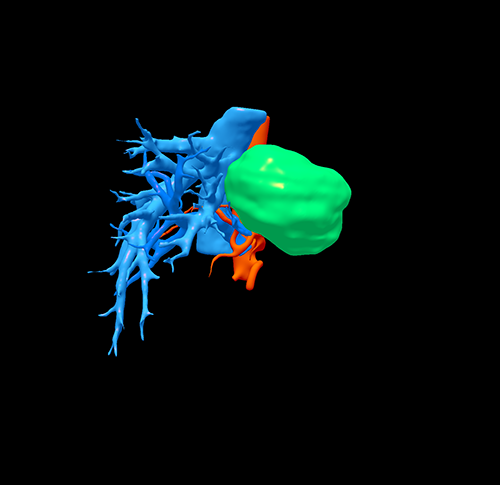

左肝肝癌---扩大左半肝切除+尾状叶切除